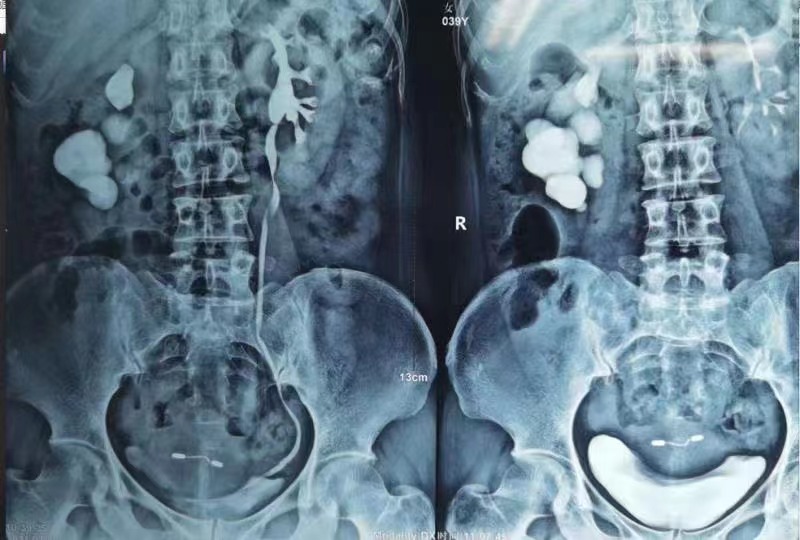

肾结石的危害有多大?近日,云南结石病医院接诊了一位肾结石患者,53岁王阿姨。王阿姨到院做系统检查时,X光片拍出来把她自己吓了一跳,王阿姨的结石被专家称为“铸型结石”,已经生长了20多年,长成了珊瑚形状,两颗肾脏的所有通道被满满塞住!

王阿姨慕名来到了云南结石病医院,求医泌尿外科专家黄丽娟主任。在医院做了进一步的结石检查后,黄主任发现,王阿姨的结石形状如“珊瑚”,布满了双肾内的肾盂肾盏,已经引起了肾脏黏膜破损溃烂和中度肾积水,属比较复杂的巨大铸型结石,肾功能也受到了一定程度的损伤。黄主任表示,王阿姨需尽快手术取出结石,再拖延下去,可能会有丢命的危险。

入院一天后,黄主任为王阿姨做了第一次微创经皮肾镜取石手术,取净了左肾结石;一周后,黄主任又为其实施了第二次手术,将右肾结石一网打尽。两次手术从王阿姨体内取出激光击碎后的“珊瑚”碎石,重量竟达5两。王阿姨高兴地告诉记者,“非常感谢黄主任,没有你们,我的肾脏估计就保不住了!”